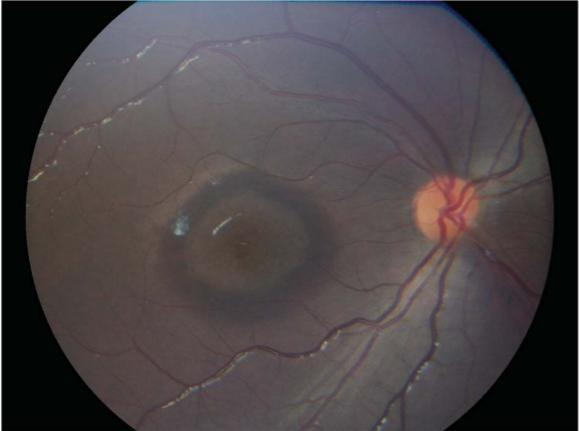

专科检查:右眼最佳矫正视力为20/100;左眼最佳矫正视力为20/40。眼前节检查无异常。两只眼睛的眼底检查均显示黄斑部有黄斑牛眼征,环形古铜色区域外有一圈紫红色(图 1 , 2)[1]

这不就是典型的“牛眼症”!

因此,这个患儿最终诊断为:“Ferritin Retinopathy”  "铁蛋白视网膜病变"。这也给广大眼科医生提醒,虽然儿童和年轻人的牛眼黄斑病变在大多数情况下可诊断为遗传性变性,但仔细检查黄斑中的牛眼形态、询问病史和药物使用史也是必不可少的。